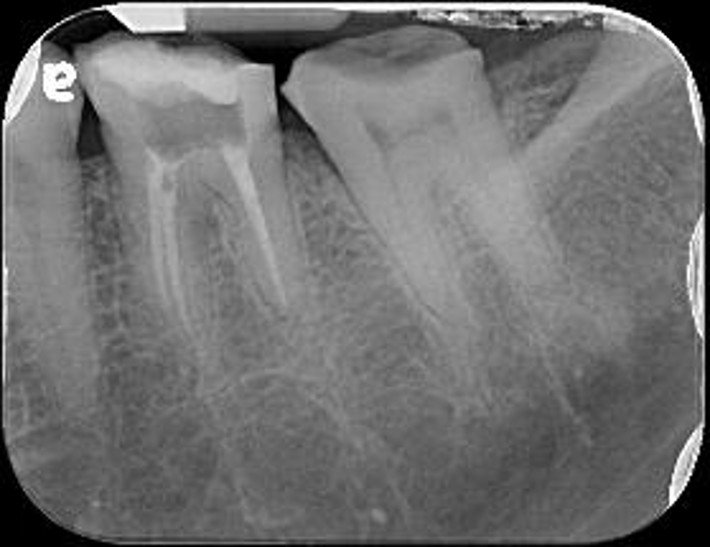

治療前,原根管治療已再污染

牙冠增長手術-#36

牙冠增長手術-#37